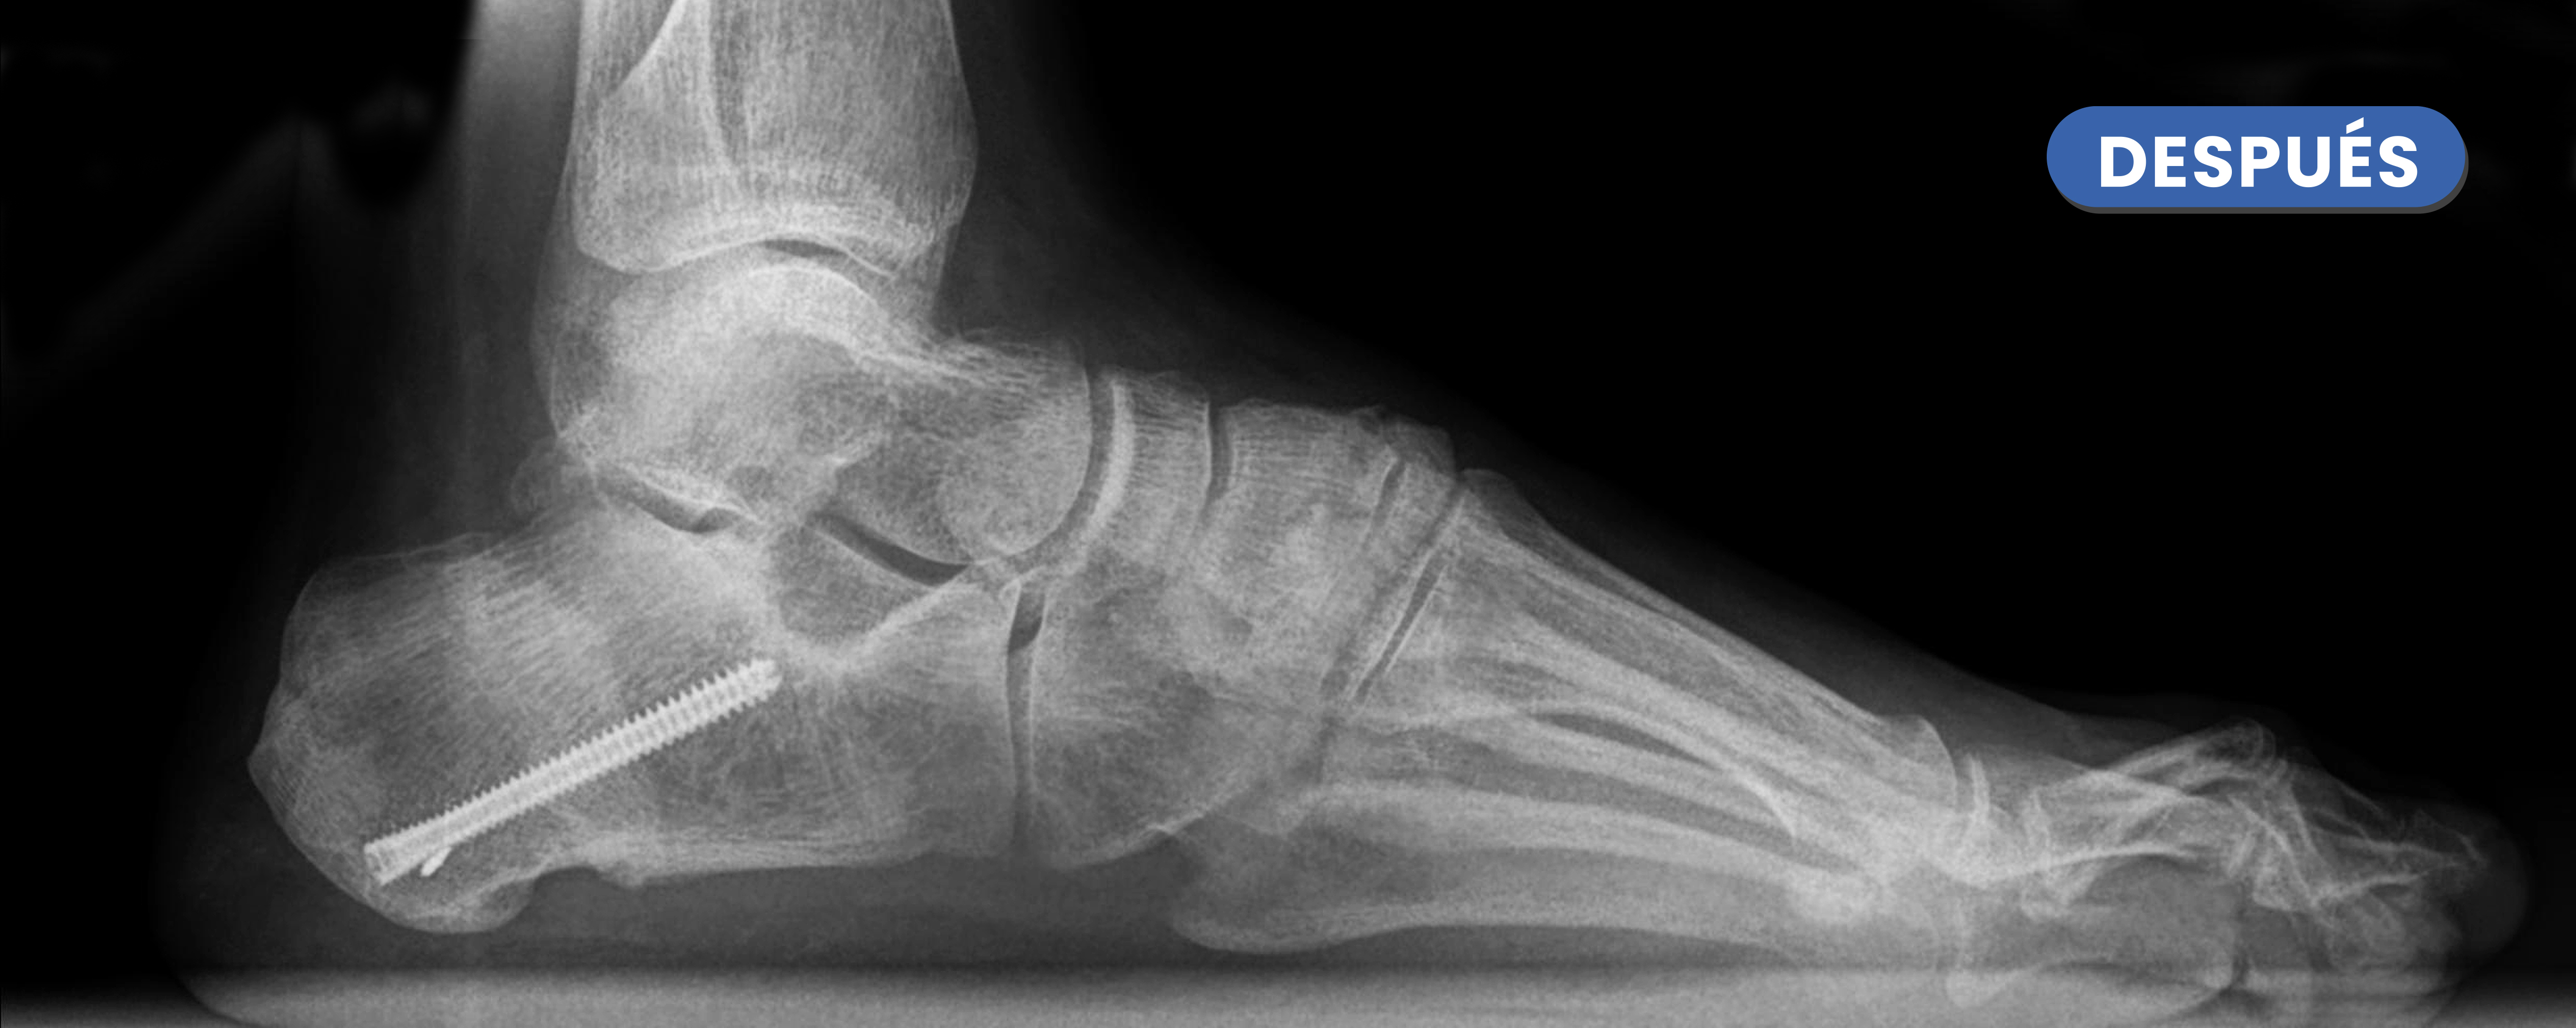

Te mostramos casos reales resueltos mediante cirugía de mínima incisión por el Dr. Rubén Lorca y su equipo.

Mueve las flechas para visualizar el antes y después.

En estas radiografías se puede observa el aumento de tamaño del arco interno (ALI ) tras la realización de la osteotomía varizante fijada mediante un tornillo.